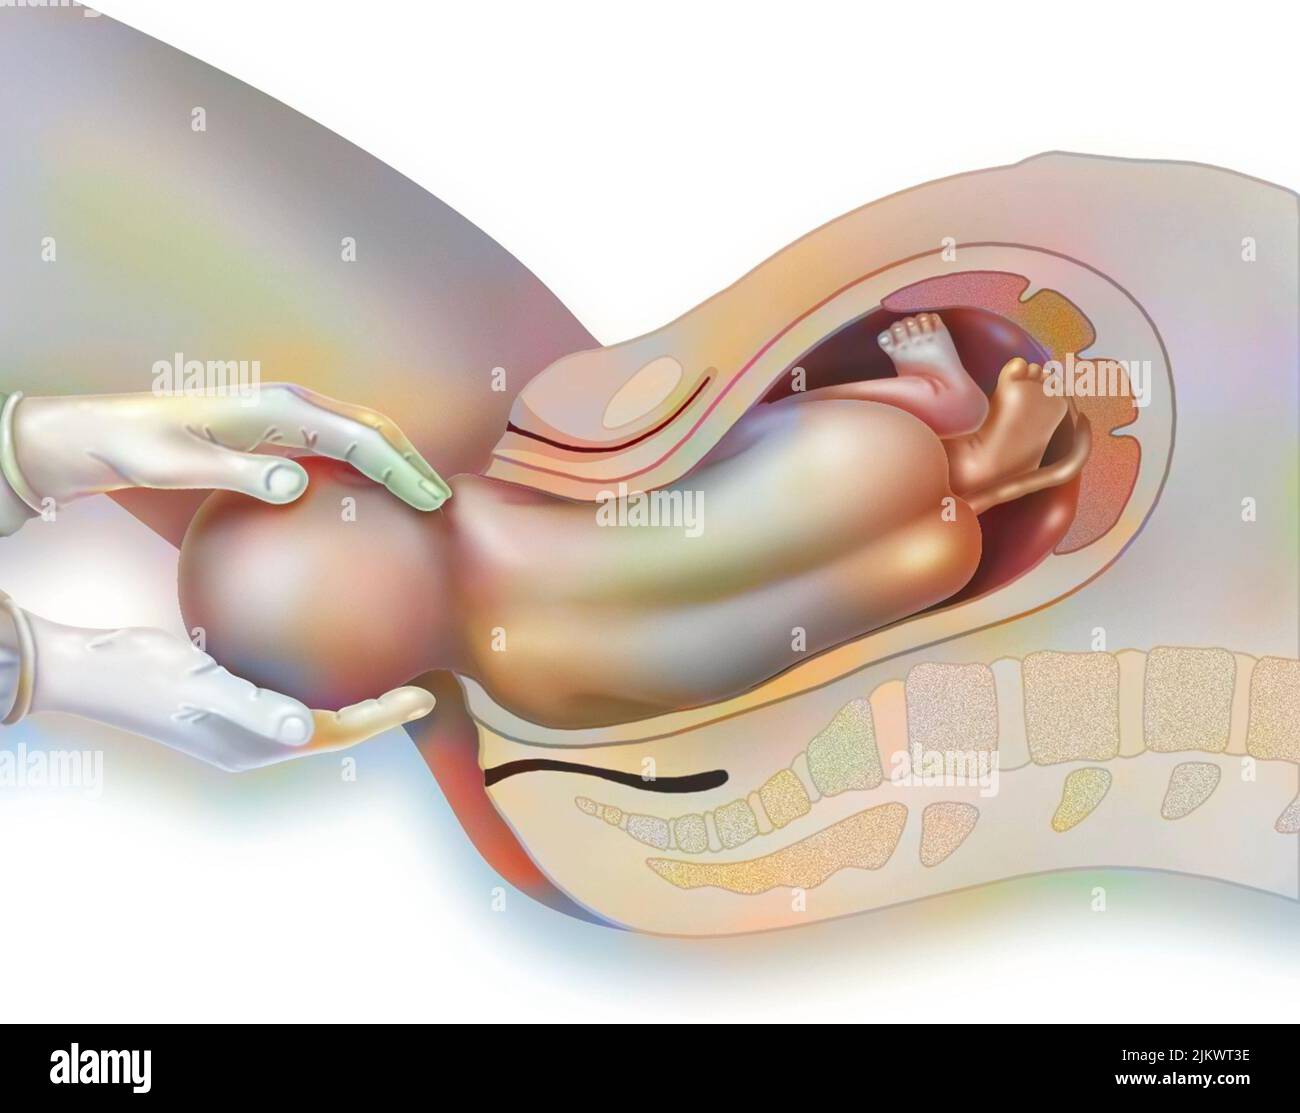

RF2JKWPFD–Auto-échantillonnage vaginal : l'écouvillon humide est administré au médecin pour analyse.